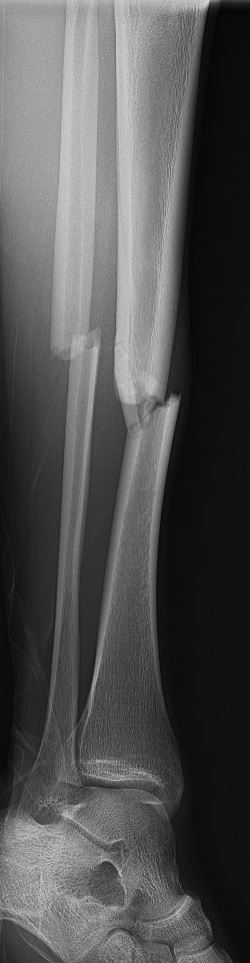

Het onderbeen bestaat uit twee lange botten; het scheenbeen en het kuitbeen. Het scheenbeen vormt samen met het bovenbeen het kniegewricht en het scheenbeen en het kuitbeen samen vormen met de voet het enkelgewricht. Het scheenbeen is vele malen dikker en sterker dan het kuitbeen en draagt veruit het meeste gewicht van het lichaam.

Omdat het scheenbeen een erg sterk bot is, is er vaak veel energie nodig om het onderbeen te breken. Vaak gaat het om een verkeersongeval, een val van hoogte, maar ook soms een harde directe trap tegen het onderbeen. Bij een breuk van het onderbeen is er in principe sprake van een breuk van zowel het scheenbeen als het kuitbeen. Soms is alleen het scheenbeen gebroken. Indien alleen het kuitbeen gebroken is, spreken we niet van een onderbeenbreuk, maar meestal is er dan sprake van een gebroken enkel of een geïsoleerde kuitbeenbreuk. Omdat bij een onderbeenbreuk meestal beide botten gebroken zijn, is er vaak sprake van instabiliteit van het onderbeen. Behalve een letsel van het bot is er ook vaak letsel van de zogeheten weke delen, zoals huid, pezen, spieren en eventueel zelfs bloedvaten of zenuwen. Indien er sprake is van een ernstig letsel van de weke delen, kan dit leiden tot een open breuk (het bot komt dan in contact met buitenlucht) of zelfs uitval van de zenuwen en/of bloedvaten.

Omdat er meestal sprake is van instabiliteit en verplaatsing van de breukdelen, is een operatie bij volwassenen meestal noodzakelijk. Afhankelijk van de stand van de breuk en de toestand van de weke delen, kan uw traumachirurg besluiten dat dit met spoed moet gebeuren, of dat dit enige tijd kan worden uitgesteld en uw onderbeen tot aan de operatie tijdelijk wordt gestabiliseerd in gips (vanaf het bovenbeen tot en met de enkel).